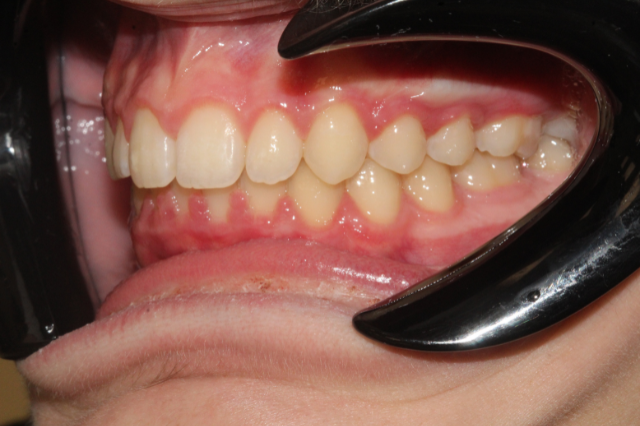

Fogív rendezés

A frontfogak torlódását és a harapás eltérését sikeresen korrigáltuk, így a fogív szabályossá vált, a rágófunkció javult és az esztétikai megjelenés is sokkal harmonikusabb lett.

Fogiv-rendezes-elott

Fogiv-rendezes-utan

Előtte

Utána